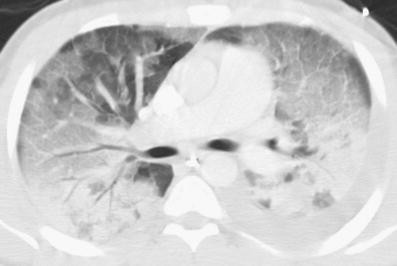

Ct Links Vaping To Ards In New Case Studies

Ct Links Vaping To Ards In New Case Studies from www.auntminnie.com

Acute Respiratory Distress Syndrome Radiology Reference Article Radiopaedia Org

Acute Respiratory Distress Syndrome Radiology Reference Article Radiopaedia Org from prod-images-static.radiopaedia.org